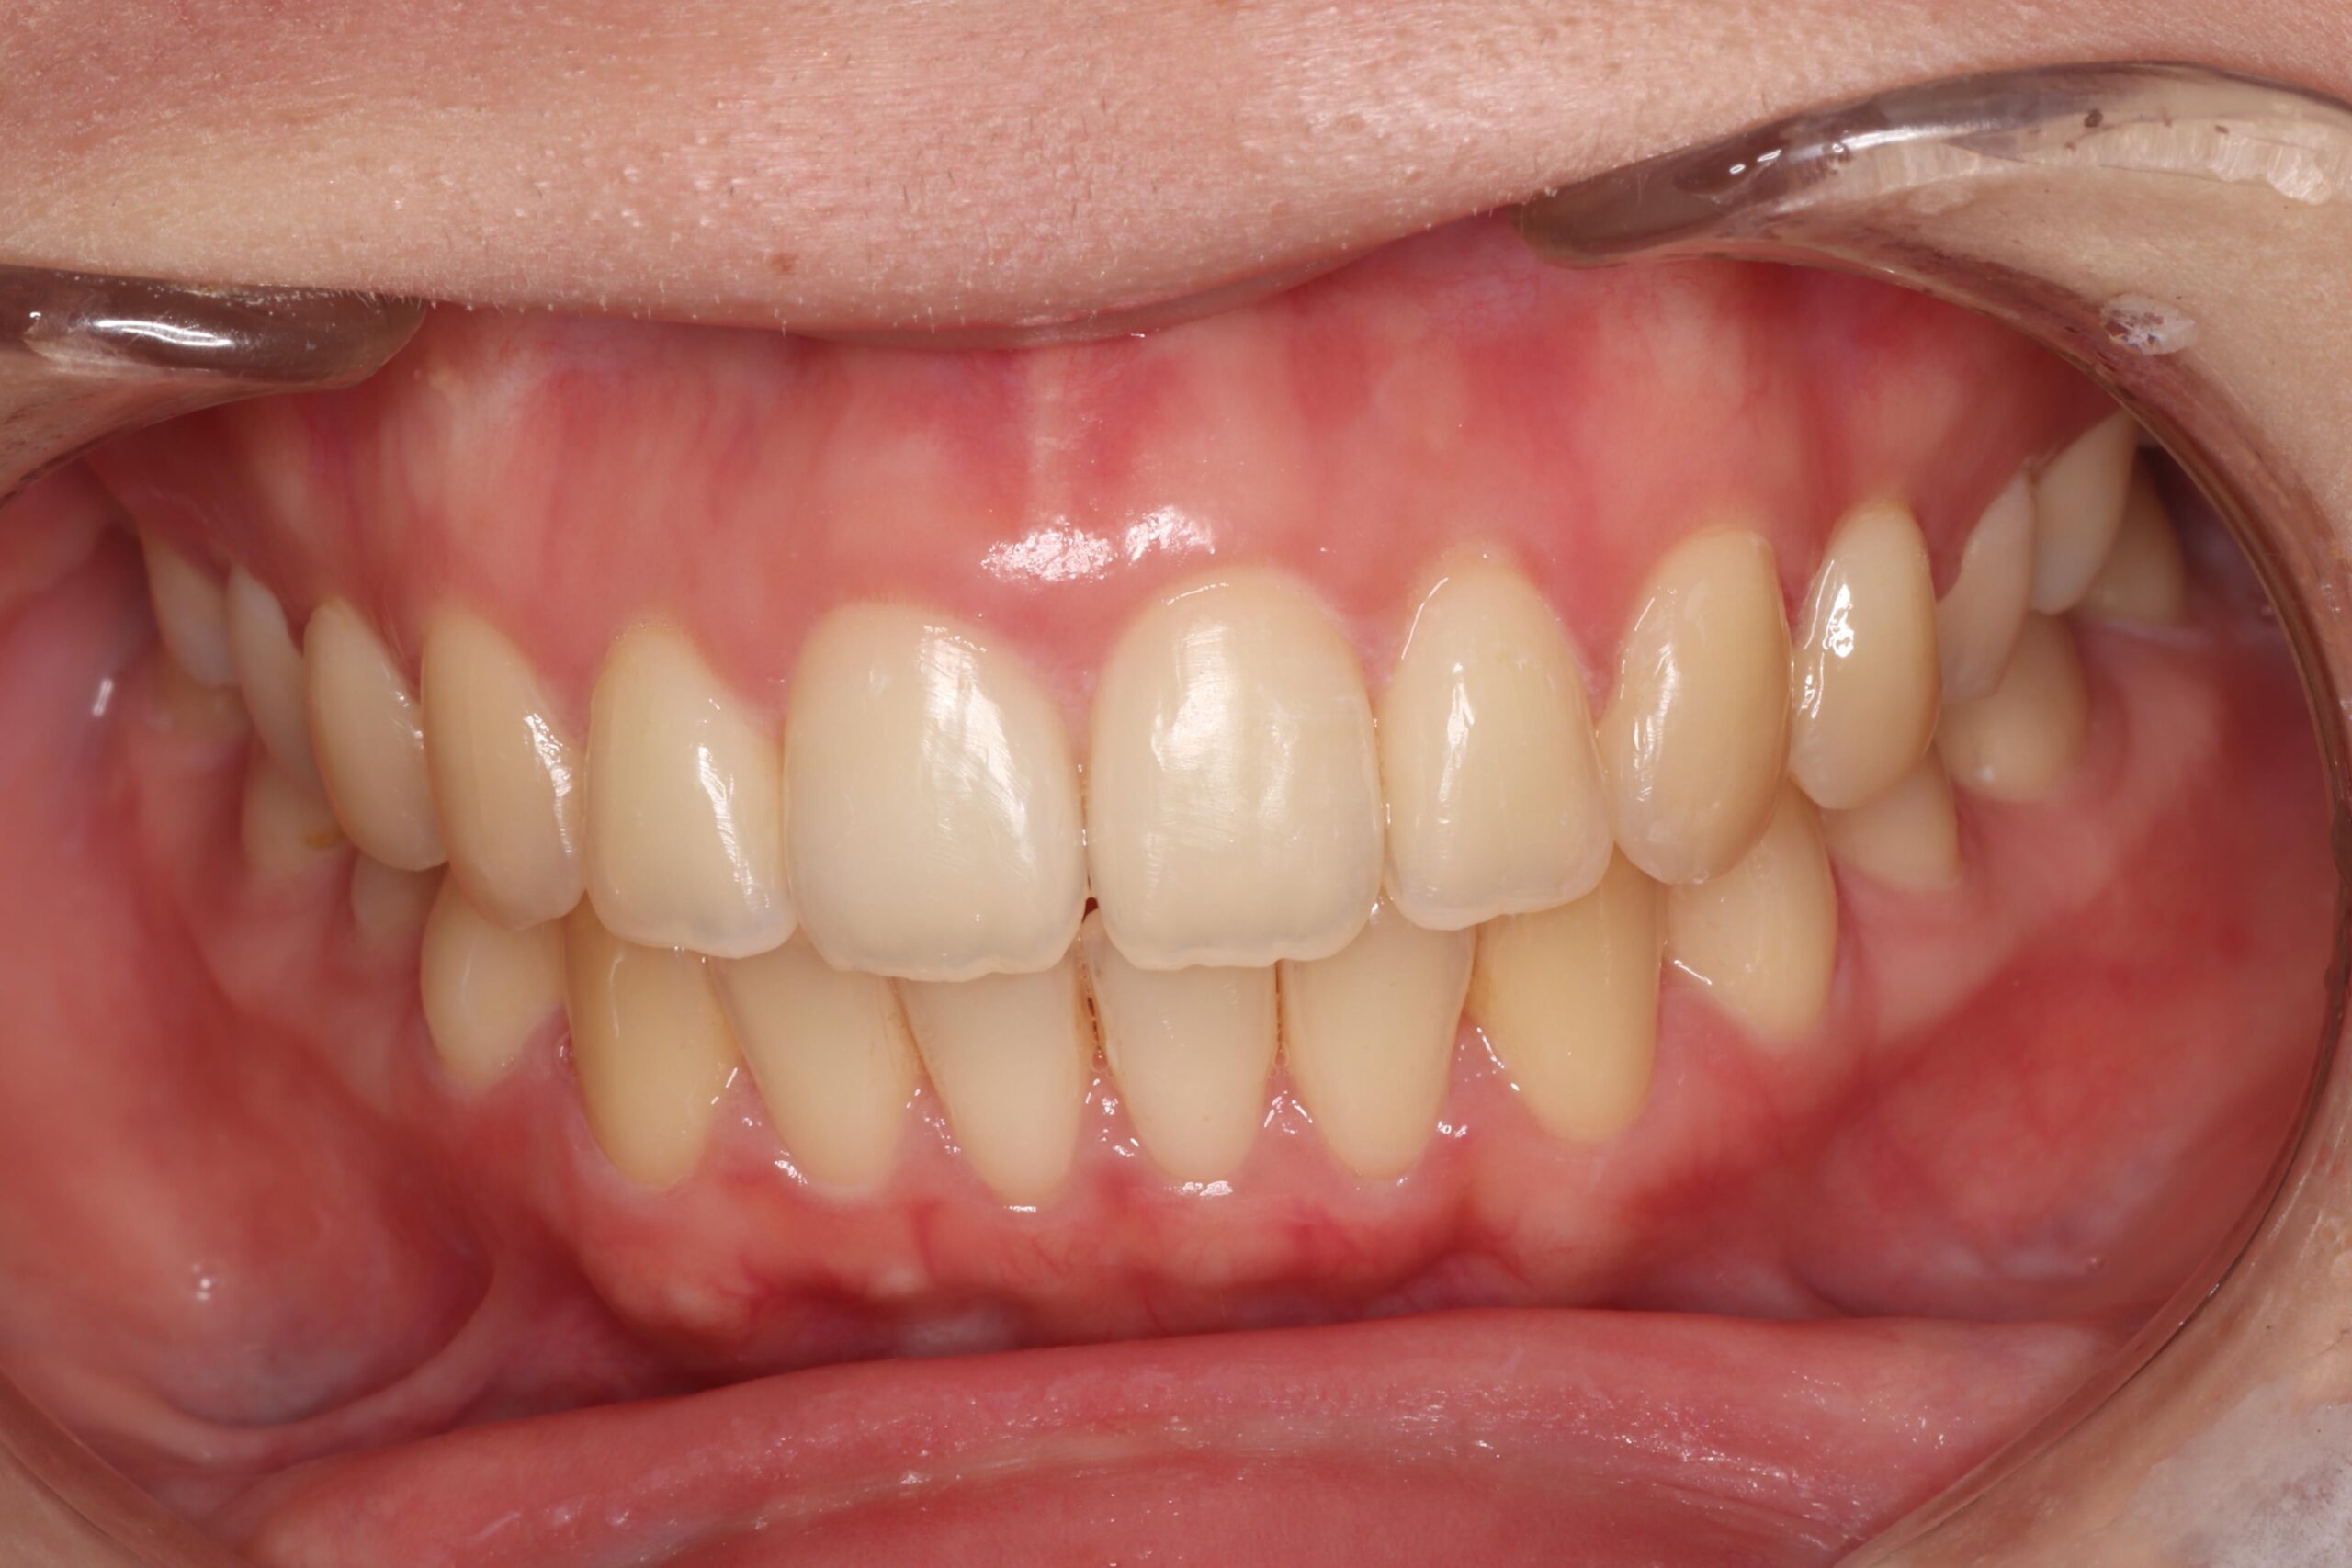

犬歯が外側に飛び出して、他の歯に重なっている状態です。八重歯は噛み合わせに問題が生じたり、歯磨きがしにくいことでむし歯や歯周病の原因となることがあります。